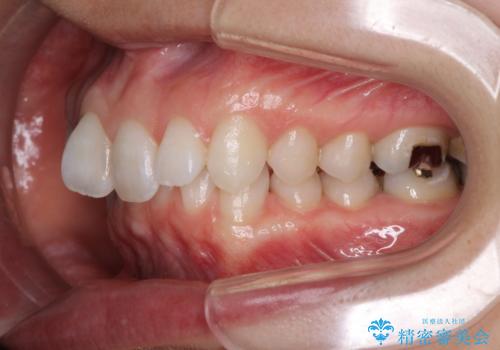

- 奥歯の虫歯と前歯のデコボコや突出感を気にして来院された患者様です。

矯正治療後は、奥歯の虫歯や銀歯を補綴・修復治療することとしました。

上顎歯列を下顎に対して4mmほど移動させる必要があったため、治療は長期化することが予想されましたが、患者様にはこちらの期待以上にゴムかけなどに協力いただき、補綴治療も含めて2年強で終えることができました。